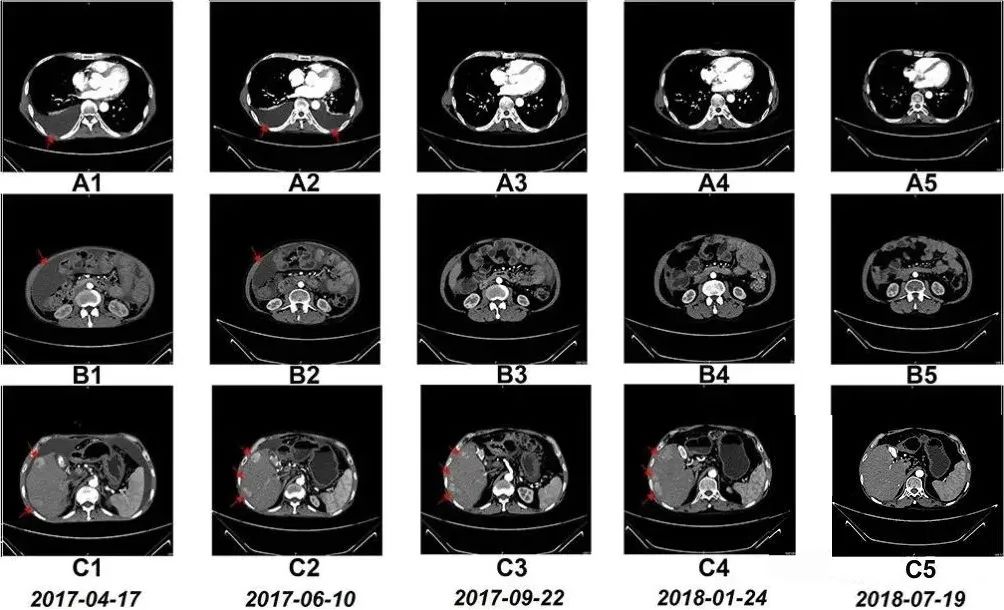

59岁的程先生连续几日右上腹出现持续性刺痛,加上就诊前有恶心、腹泻、发热等症状,提心吊胆的他在家人陪伴下来到医院检查,不查不知道,一查吓一跳,检查结果显示:胸腔积液(胸水)、腹腔积液(腹水)、肝右叶有多个肿瘤,程先生最后被确诊为弥漫性肝癌晚期(IV期)。

随后的8个月里,患者接受了一系列的手术、化疗和药物治疗。2017年3月,他开始尝试NK细胞输注治疗,值得一提的是,患者在NK细胞治疗期间,除营养支持、心理干预等辅助疗法之外,未接受其他治疗。

令患者本人和医疗团队都格外惊喜的是,7个月后,患者的胸水和腹水明显减少,治疗17个月后,CT扫描显示他肝右叶的多个肿瘤显著缩小。淋巴细胞亚群出现的变化表明免疫功能得到改善。此外,患者的肝功能水平和白细胞、血小板、中性粒细胞和淋巴细胞计数也保持在参考范围内。

更难得的是,据研究小组跟踪获悉,截至发稿,患者目前仍带瘤生存。

“治疗过程中没有出现发烧、呕吐等不良反应,”主治医生在病例报告中特别指出,“ 但最让我们感到欣慰的是患者的生活质量显著提高。”

上文提到的晚期肝癌患者程先生,正是通过15个月的NK细胞输注,使体内NK细胞比例提升近7倍,同时CD8+T细胞等关键免疫指标显著改善。影像学检查显示其胸腹水消退,肝部肿瘤缩小,生存期远超预期。